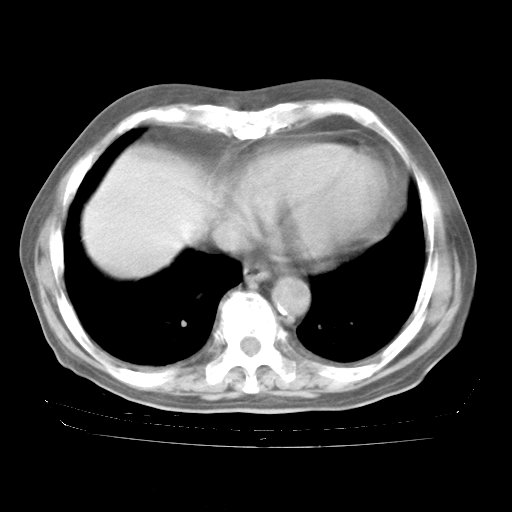

今天部分检查

轻微咳嗽,无痰,(体温正常时)R20次/分,P75次/分,双肺底、腋下可闻及少量捻发音。下肢轻度浮肿。

腹部B超:胆囊壁增厚,肝、胆、胰、脾、肾无异常,肠系膜淋巴结、腹膜后淋巴结无增大。

ECG:右心室增大

心脏超声检查:无右心室增大。